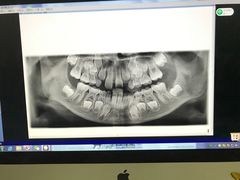

• 德伦口腔

• -德伦口腔

Gattaca | 17-04-30

报错